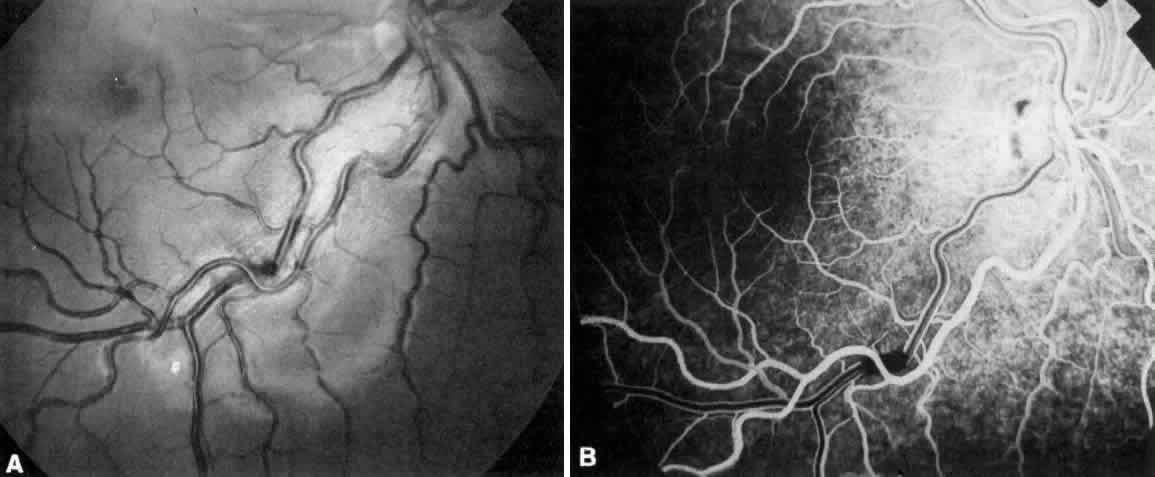

Cyanotic CHD when associated with severe hypoxemia and erythrocytosis may

result in retinal and disc edema, as well as vascular (primarily venous) tortuosity.76 Severe erythrocytosis (hematocrit in the high 60s and greater than 70% may

lead to severe vascular dilatation and tortuosity that mimics central

retinal vein obstruction; retinal and disc edema may result (Fig. 1). Cerebral abscess occurring in this population may also be present with

retinal and disc edema.